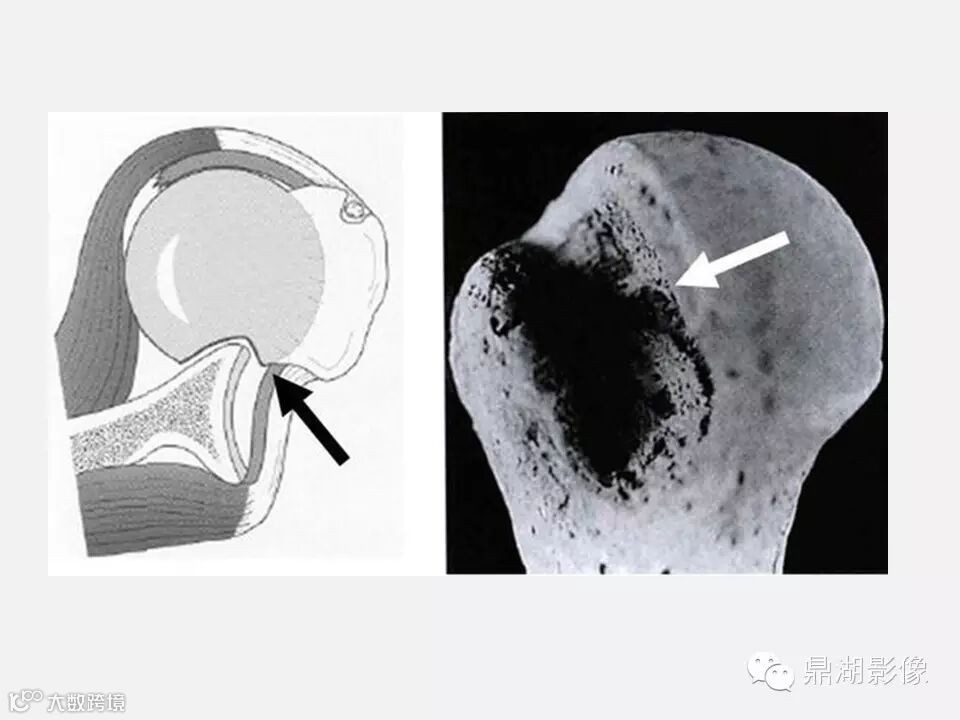

【聚沙成塔】Hill-sachs骨折知多少?